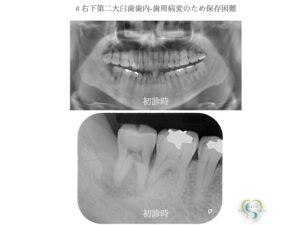

‎20260312_自家歯牙移植.‎002 | さとう歯科クリニック 南区妹尾